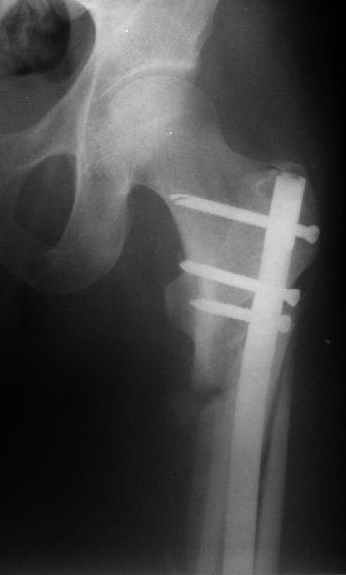

При межвертельных переломах с цефаломедуллярными гвоздями бывает, что проксимальый винт проходит или черед периферический отломок, или прямо над ним. И если остался диастаз, то этот винт при осевой нагрузке не дает сблизиться отломкам. Пример такого остеосинтеза в застарелом случае в приложении.

В качестве предупреждающей меры можно долотом разрушить латеральную стенку дистального отломка под винтом.

В частности, на проксимальном конце сделано еще одно дополнительное статическое отверстие. Можно ввести в проксимальном отделе 4 винта, из них 3 статические (2 в круглые отверстия и 1 по нижнему краю овального). Картинки в приложении. На дистальном конце стержня тоже кое-что улучшено. Спрашивайте в аптеках, как говорится. Выпускается предприятием "ЦИТО" (Москва), то есть это малобюджетное решение.

Конечно, мы не синтезируем остеопорозые вертельные переломы согласно прилагаемому примеру, винты 6 мм вырежутся. Но у более молодых при хорошем качестве кости такие или подобные гвозди с поперечным расположением винтов вполне применимы для меж- и подвертельных переломов.

Женя, эта картинка показывает не оптимальное лечение вертельных переломов в моем представлении, а особенности дизайна упомяутого фиксатора.

В частности, его возможности при фиксации переломов проксимального отдела бедра - в сравнении с другими, имеюшими лишь по одному статическому и динамическому отверстию и с кондуктором для введения 2 винтов.

Это было года 2,5 назад, мы тогда еще уточняли возможности шинирования с угловой стабильностью гвоздем с поперечным расположением винтов при переломах проксимального отдела бедра. Пациенту не пришлось приобретать намного более дорогой рекон или проксимальный гвоздь. В приложении еще несколько примеров применения того гвоздя при высоких переломах бедра, в том числе с более латеральной точкой входа. Гвоздь изгибаем для этого.